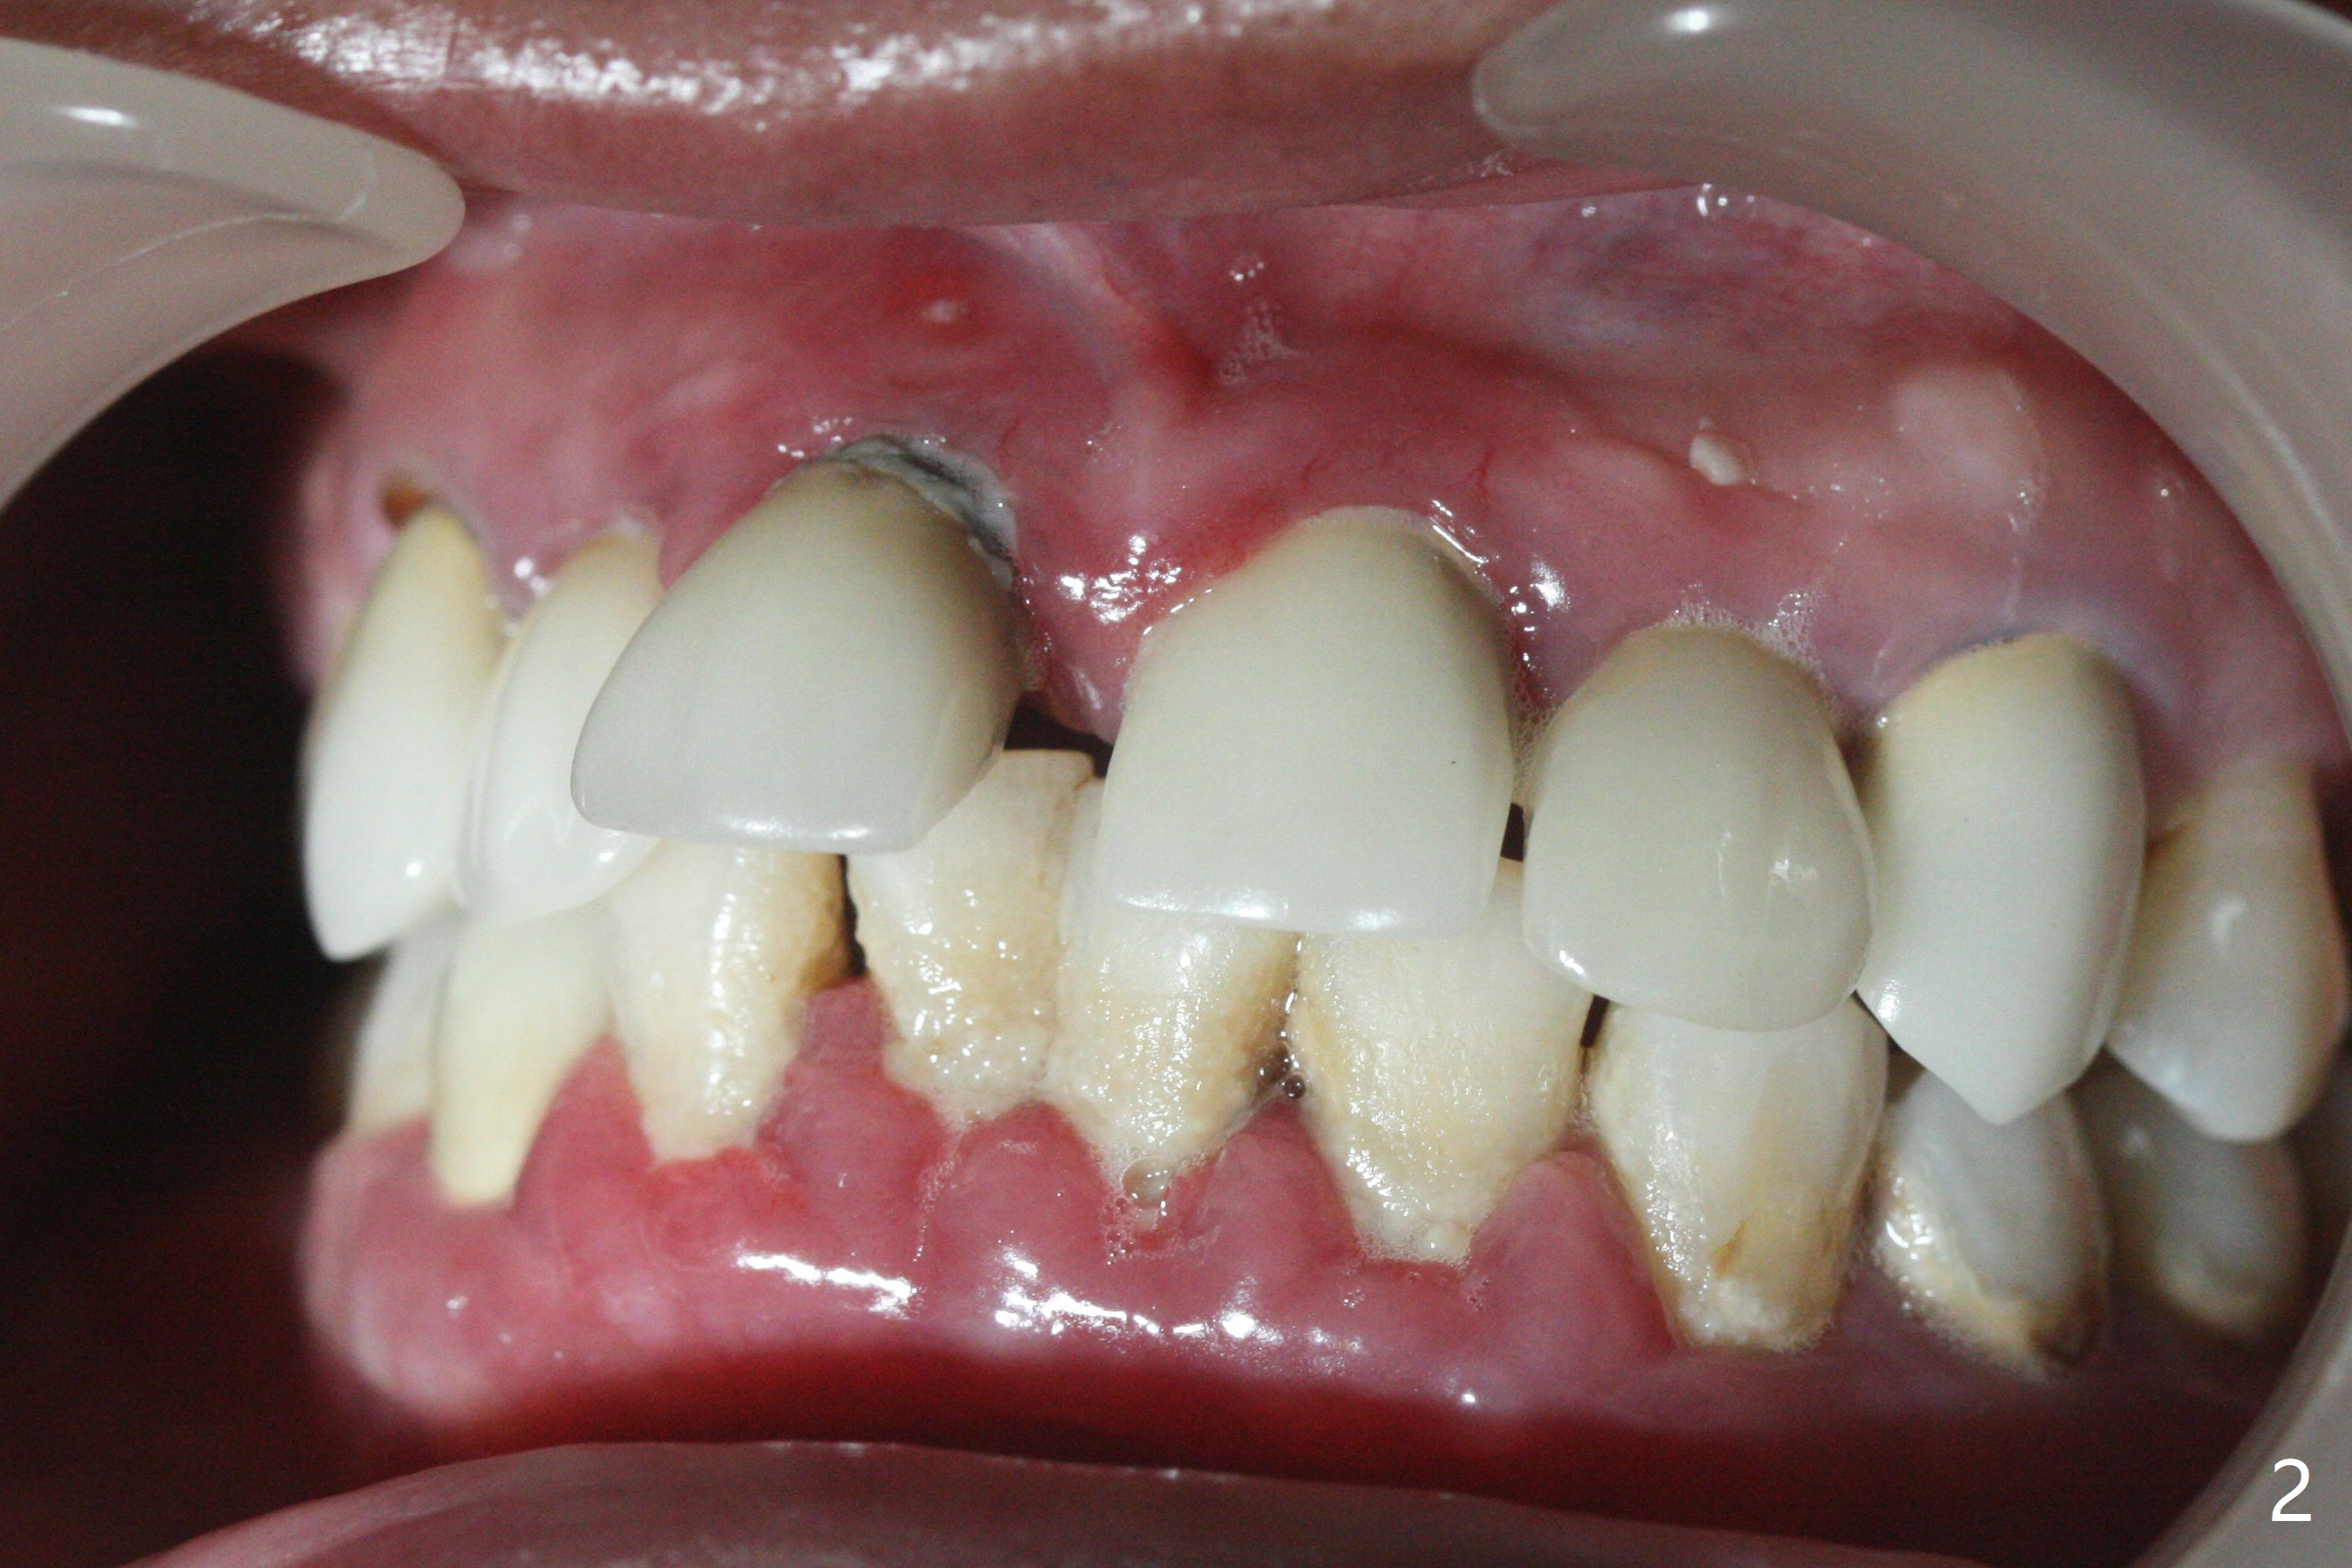

45岁女,害怕治疗,5年多没就医,右上1移位(图一(*),二),严重骨吸收(图三)。深洗后,即刻种植,由于牙龈7毫米长(图四,五)和使用粘性骨粉(骨壁再生),植体可以植浅些(图四:箭头)。上颌深洗一周后,除了患牙,牙龈红肿消除很多(图六,七)。